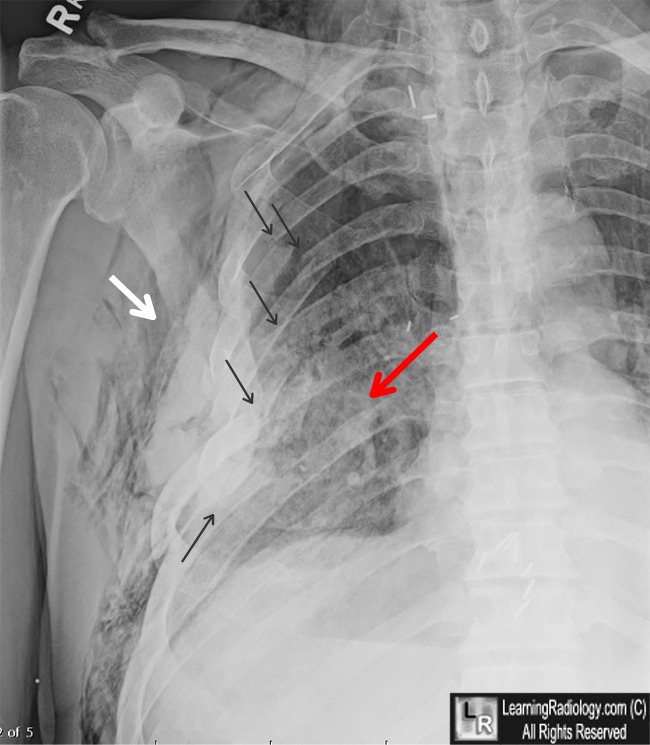

From www.learningradiology.com

LearningRadiology Rib Fracture Without Trauma  However, almost any underlying process of. Although painful, a hairline fracture in one of these bones may heal without treatment. Rib fractures can occur with or without direct trauma during recreational activity. In a study of 552 patients who had blunt chest trauma and resultant rib fracture (diagnosed on clinical or radiographic grounds), 93% of. Consult our lung & chest. Rib Fracture Without Trauma.